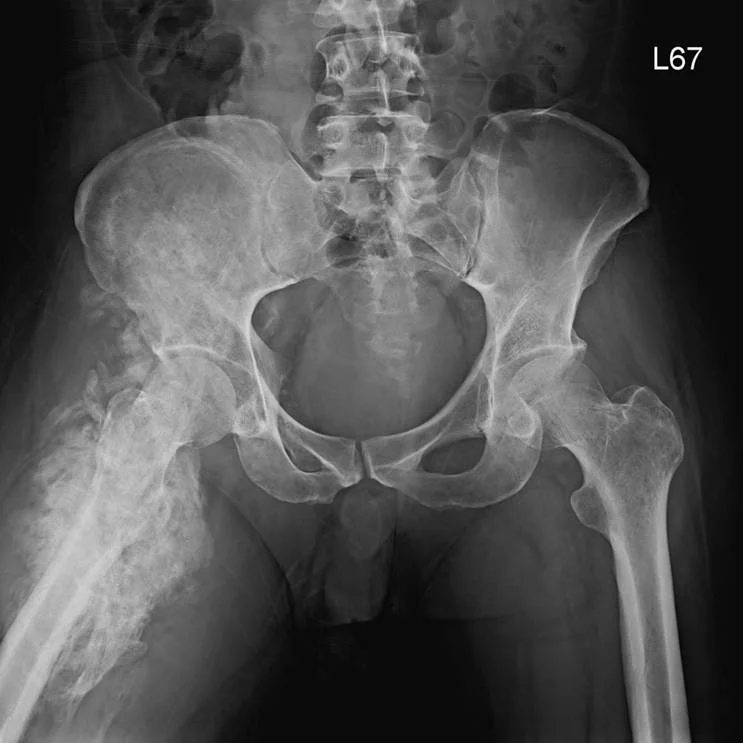

這張X光片最關鍵的線索是右側髖部周圍軟組織出現大片不規則、緻密的骨化影像,結合病患中風後右半側癱瘓的病史,強烈指向異位性骨化。